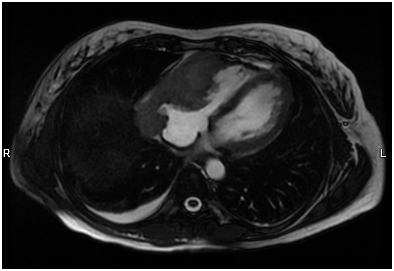

A 55-year-old African American woman presented with a one-month history of progressive exertional dyspnea and chest tightness. She had no significant past medical history. An echocardiogram revealed a large pericardial effusion and features of cardiac tamponade. A cardiac CT scan (Figure 1A) showed a mass at the pericardium extending into the right ventricular myocardium. Multiple bilateral lung nodules were noted with the largest measuring 1.6 cm in diameter.

A pericardial catheter was placed and a large bloody effusion was drained. A cardiac MRI (Figure 1B) revealed a 10 cm infiltrating soft tissue mass involving the right atrium and right ventricle. The right coronary artery was encased and attenuated. The mass extended into the atrioventricular groove and infiltrated the roof of the right ventricle. The anterior surface of the aortic root was also encased. Heterogeneous enhancement of the mass suggested a vascular lesion suggestive of angiosarcoma.

The patient was taken to the operating room where, via a limited right infra-mammary incision and under general anesthesia, pericardial window (Figure 1C) biopsies of the adherent pericardium, the mass invading the right ventricle, and a pulmonary wedge resection of nodules in the right lower lobe were made.